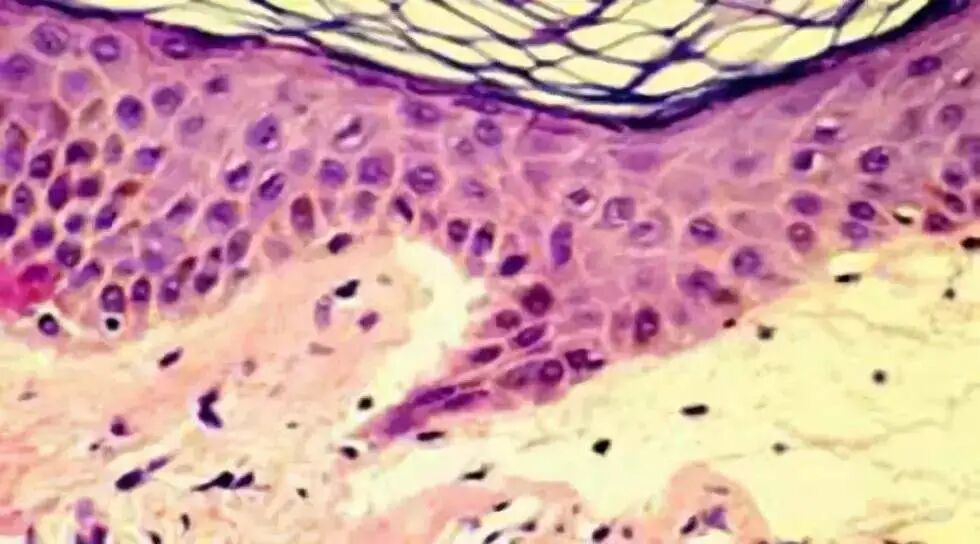

皮肤是人体的重要器官,它起着控制体温 ,防止感染及体液流失,免疫及传感的作用。由于创伤、擦伤、皮肤 溃烂和烧伤等原因,可能导致皮肤的大范围伤害。皮肤的损伤容易造成细菌感染,体液流失并引起各种并发症。通常采用伤口敷料对伤口进行保护,防止伤口的感染和脱水,在伤口处维持有利于治疗的潮湿环境,改善治疗效果,促进伤口愈合。

1.促进与创面愈合相关细胞的生长,如促进正常成纤维细胞、上皮细胞和角质细胞的生长;促进巨噬细胞产生有助于创面愈合的活性因子,从而促进创面愈合;

2.促进皮肤创伤组织的微血管再生,改善血液循环,从而加速创面愈合;

3.壳聚糖敷料与细胞间质中粘多糖类基质的分子结构相近,细胞相容性好,为皮肤细胞的生长提供了有利的环境,有利于创面的愈合。